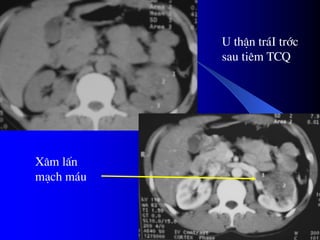

- CLVT phán biãût khäúi âàûc hay dëch, phaït hiãûn

väi hoïa nhoí, xuáút huyãút trong u, tçnh traûng

tæåïi maïu cuía u.

Pháön låïn træåìng håüp phán biãût âæåüc u laình vaì

u aïc.

Xem xeït âæåìng dáùn niãûu bë giaîn, bë xám láún.

CLVT kiãøm tra di càn haûch xám láún vuìng

xung quanh, xám láún maûch maïu, di càn xa,

cå såí âãø phán giai âoaûn tiãún triãøn u, cáön

thiãút cho phæång phaïp âiãöu trë.